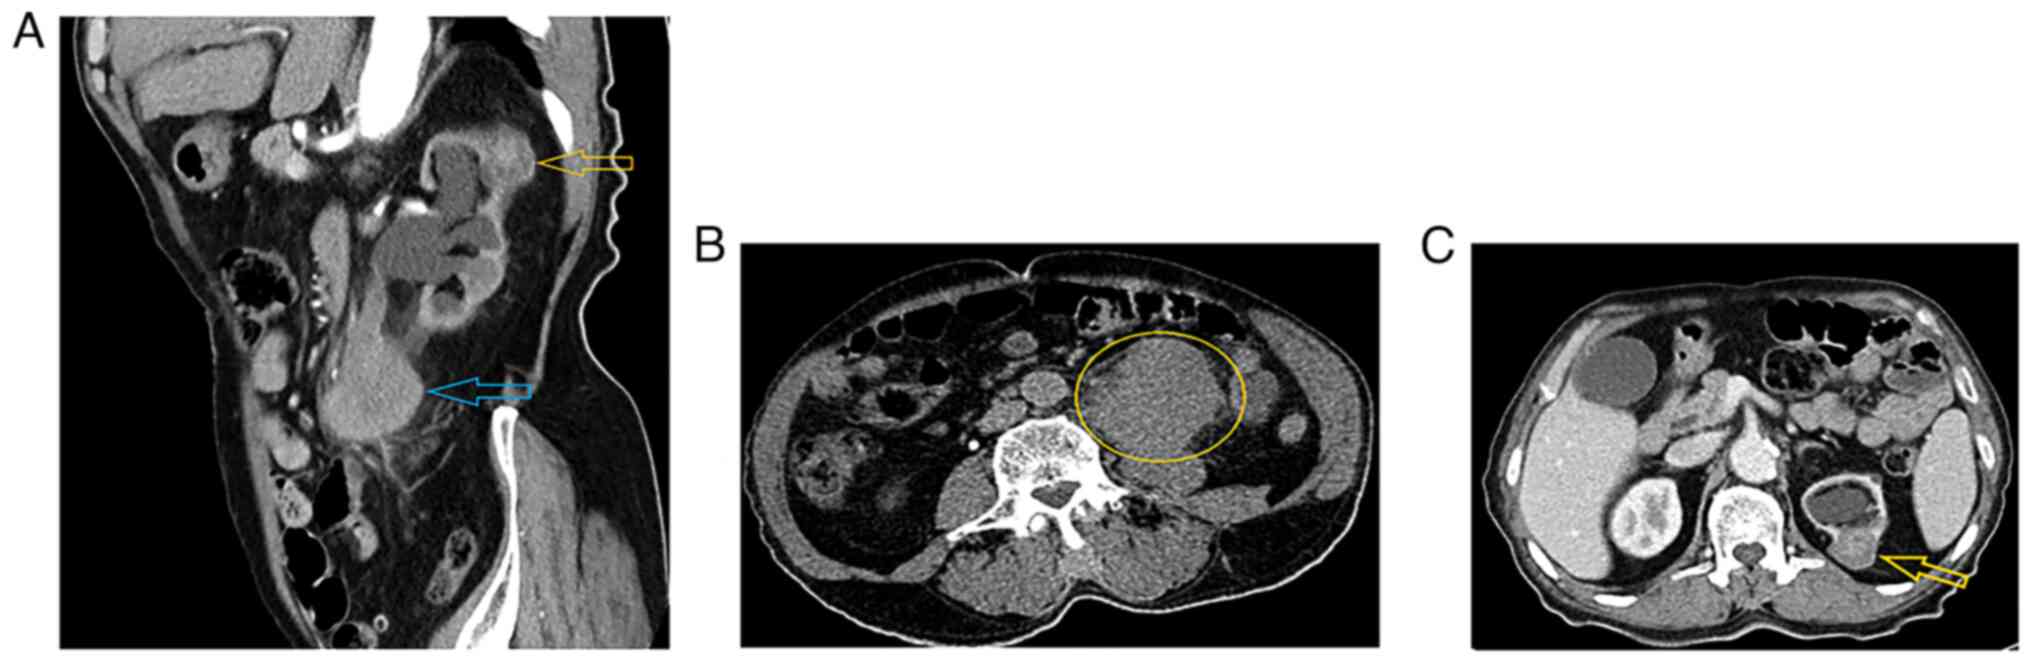

Blood investigations showed the following results: White blood cells (WBCs), 17×1010 (reference range, 4–11×109/l); hemoglobin, 12 g/dl (reference range, 13.0-18.0 g/dl); blood urea, 63 mg/dl (reference range, 8–23 mg/dl); serum creatinine, 1.4 mg/dl (reference range, 0.6-1.2 mg/dl); glucose, 121 mg/dl (reference range, 70–110 mg/dl); and C-reactive protein, 25 mg/dl (reference range, <5.0 mg/l). An ultrasound scan of the abdomen and pelvis revealed moderate to severe left hydronephrosis with decreased renal cortical thickness and hydroureter to the level of a 54×41-mm hypoechoic mass located 4 cm away from the left ureteropelvic junction. A contrast computed tomography (CT) scan of the abdomen and pelvis demonstrated two masses. A 60×50×48-mm mass was identified at the left upper and mid ureter, showing heterogeneous enhancement, causing proximal ureteric and pelvicalyceal system dilatation with parenchymal thinning and moderate to severe hydronephrosis. The disease had spread from the ureter wall to the retroperitoneum, with no surrounding organ invasion. There were only a few 7-mm para-aortic lymph nodes, but without definite pathological features. Overall, the mass was suggestive of ureteric UC. The second mass was located in the upper pole of the left kidney, measured 37×27×20 mm, was partially exophytic and exhibited a hyperdense central region with no enhancement that was probably a hemorrhage. The peripheral hypodense part showed enhancement in a delayed-phase scan, and was not associated with perinephric or peritumoral pseudocapsule invasion. Overall, it was suggestive of RCC T1a (a stage 1 tumor ≤4 cm in size according to the TNM staging system) (12) (Fig. 1). Cystoscopy was performed during surgery, and the bladder urothelium appeared normal, however multiple bladder biopsies were taken. Metastatic workup was performed, including contrast CT scans of the chest, abdomen and pelvis. There were no suspicious bone lesions found in the CT scan, and laboratory tests, such as alkaline phosphatase and serum calcium tests, were normal. Additionally, the patient had no syptoms of bone pain. According to guidelines (13,14), upper UC and RCC do not require a bone scan, so this was not performed.

Figure 1.

Contrast CT scan of the abdomen and pelvis. (A) Coronal and (B) axial sections of a delayed-phase CT scan with contrast showing a left upper ureteral mass (yellow circle). (C) Axial section showing a left upper pole renal mass (yellow arrows). The blue arrow indicates urothelial cancer in the left upper ureter.